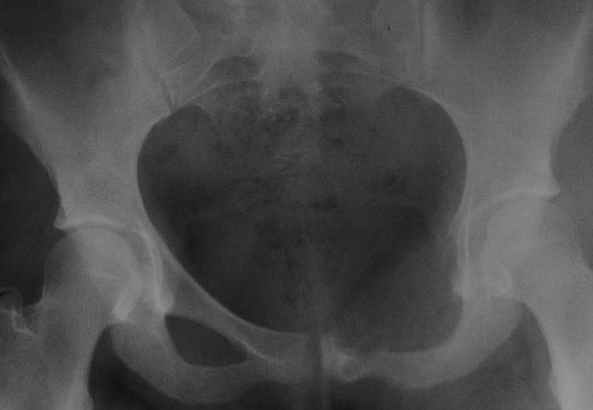

пациентка 20 лет, в сентябре 2005 года почувствовала боли в паху. На снимках заподозрили остеомиелит, лечили антибиотиками без эффекта. К онкологу попала в январе2006. Биопсия в марте 2006 - остеобластокластома. Местные онкологи от операции отказываются.

Вопрос с планом лечения (надо ли замещать деффект и чем) и где оперироваться (опыт подобных операций).В приложении рентгенограммы в динамике (2005 сентябрь, декабрь, 2006 апрель).

Показал случай нашим онкологам. Они советуют сделать КТ, чтобы выяснить распространение процесса в симфизе и вертлужной впадине. Если распространения нет, то у нас обычно просто выполняют резекцию лонной кости без замещения дефекта.